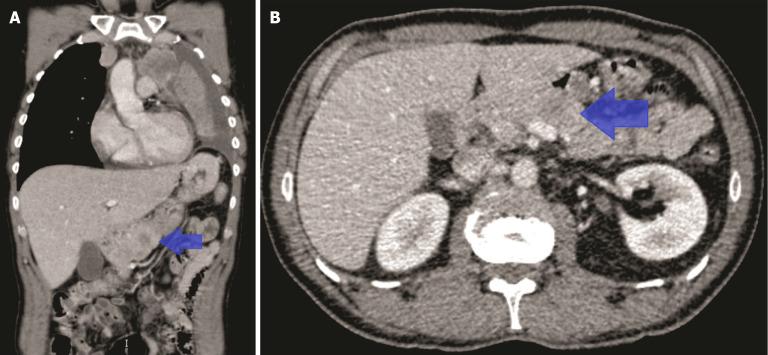

We describe the case of a 50-year-old male recently diagnosed with small-cell lung cancer (SCLC). The patient was admitted to the emergency department with acute abdominal pain and subsequently diagnosed with AP. He was hospitalized under the care of the gastroenterology service. During the etiological workup, metastatic pancreatic lesions were identified on imaging, which had not been observed on the initial cancer staging. Following resolution of the initial episode, oral intake was introduced, but the patient experienced recurrent abdominal pain and laboratory abnormalities consistent with new episodes of AP. This pattern repeated over the following days. After several episodes, and with suspicion of a metastatic origin, the case was discussed in multidisciplinary meeting. In agreement with the patient and given the need to initiate treatment for the primary tumor as well, chemotherapy was started. This treatment successfully alleviated symptoms, allowing dietary progression without complications and discharge from the hospital.

我们描述了一名50岁男性患者,最近被诊断为小细胞肺癌(SCLC)。该患者因急性腹痛入院,随后被诊断为AP。他在胃肠病科的护理下住院。在病因检查过程中,影像学检查发现了转移性胰腺病变,这在最初的癌症分期中未被观察到。初始发作缓解后,开始经口进食,但患者反复出现腹痛和实验室检查异常,与新的AP发作一致。这种情况在接下来的几天里反复出现。经过几次发作,并怀疑有转移起源后,该病例在多学科会议上进行了讨论。经与患者协商并考虑到也需要开始对原发性肿瘤进行治疗,于是开始了化疗。这种治疗成功缓解了症状,使饮食逐步恢复且无并发症,并得以出院。